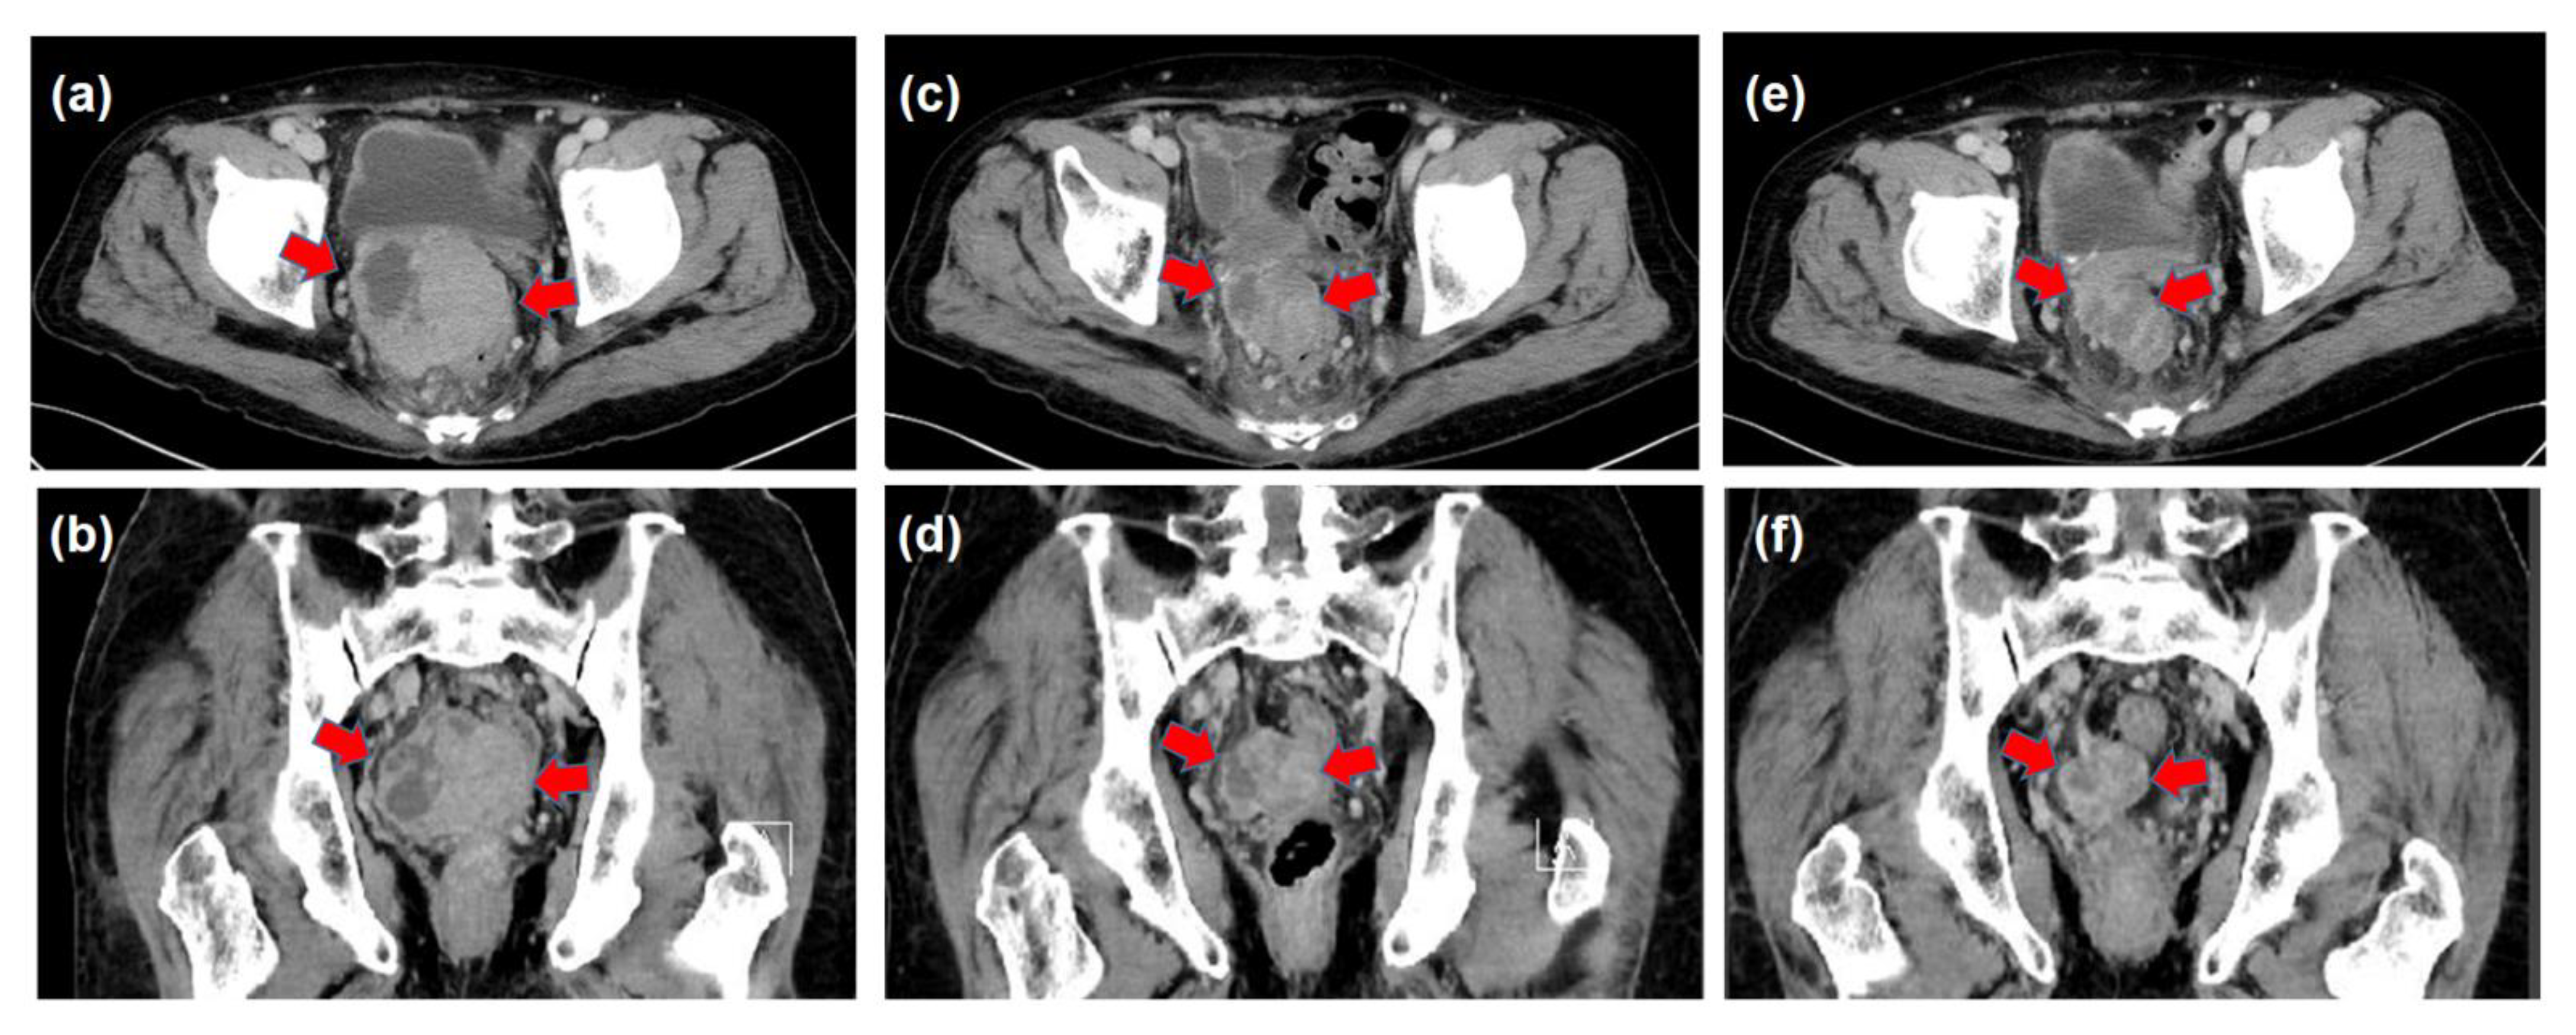

| March | Increase in the DCP and detection of the pelvic tumor Medical interview revealing mild constipation | |

| X | May | The histological diagnosis of pelvic metastasis of HCC |

| August–October | 3D-CRT (prescribed dose for the gross tumor: 60 Gy in 30 fractions) | |

| (Decrease in the tumor size and DCP values, constipation resolved) | ||